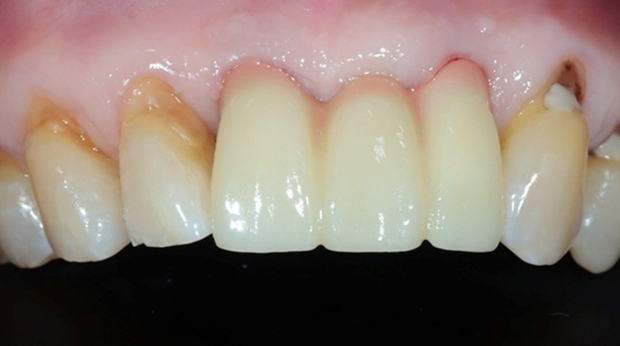

라미네이트